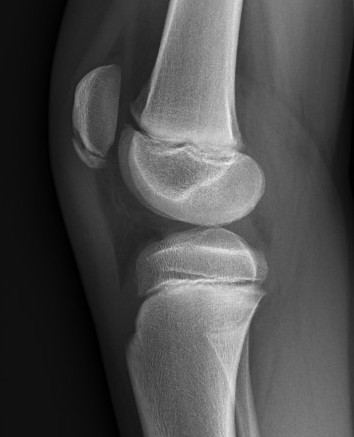

Xray

Patella alta / high riding patella

Very small bony fragment

Displaced patella sleeve fracture